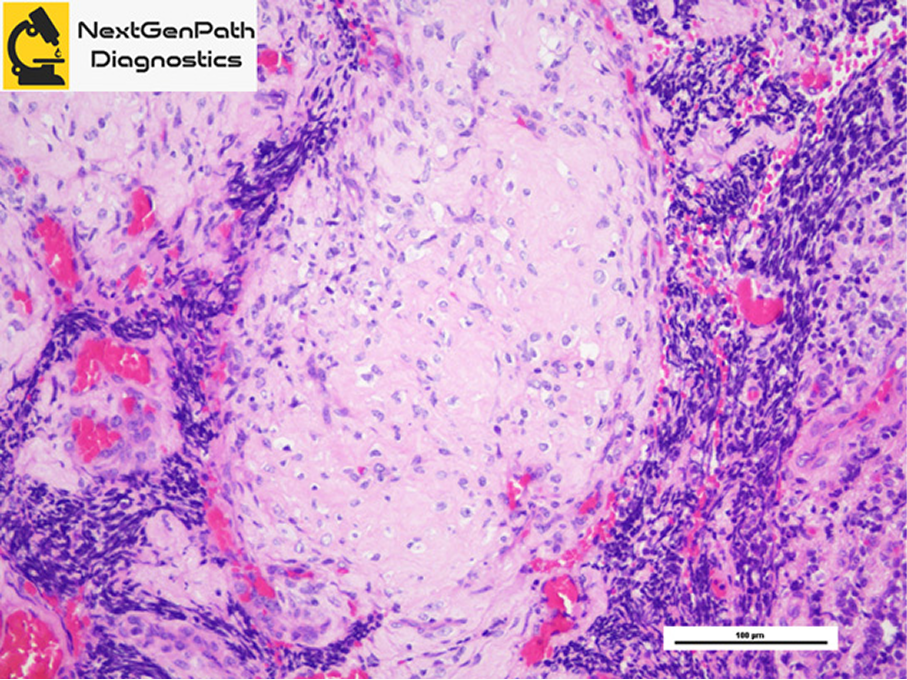

Bone and Soft Tissue Pathology

- NextGenPath Diagnostics handles a broad range of bone and soft tissue core biopsies and resections.

- Bone and soft tissue pathology interpretation requires an expert orthopedic pathologist with or without a panel of special stains immunohistochemistry and molecular studies.